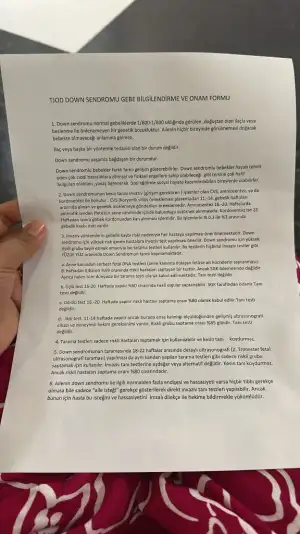

Ben bu konuda en önemli noktanıj şu olduğunu düşünüyorum.Kizlar ben bugün kontorle gittim hep bir hafta önceden söylüyordu ya doktor şimdi tam zamanını söyledi 10+6 haftalık maşallah her şey yolunda dedi. Ama fetal DNA önerdi fiyatı 15 bin mis ama bunu bir şirket yapıyor.us hastane değil sonuç 10 güne çıkıyor dedi. Bu konu da siz ne düşünüyorsunuz yaptırmalı mıyım sizce. Yaptirmazsan ikili tarama testi yapalım haftaya dedi. Çok kararsızım

Bu bebek sorunlu çıkarsa yine de doğurur muydunuz? Bu sorunun cevabı evet ise fetali geçtim ikili teste bile ihtiyaç yok.

Ama yok ben istemem derseniz o zaman düşünülmeli.Ki ben kendi adıma ikili testi yaptırırdım önce.size kuzenimin imzaladığı kağıdı yollayayım.O ikili testi bile istemedi ne olursa olsun doğurucam dedi.

Burda riskler olasılıklar yüzdelikler verilmiş.buna göre kararınızı verirsiniz.Hepimiz farklı bireyleriz farklı noktalardan bakıyoruz hayata